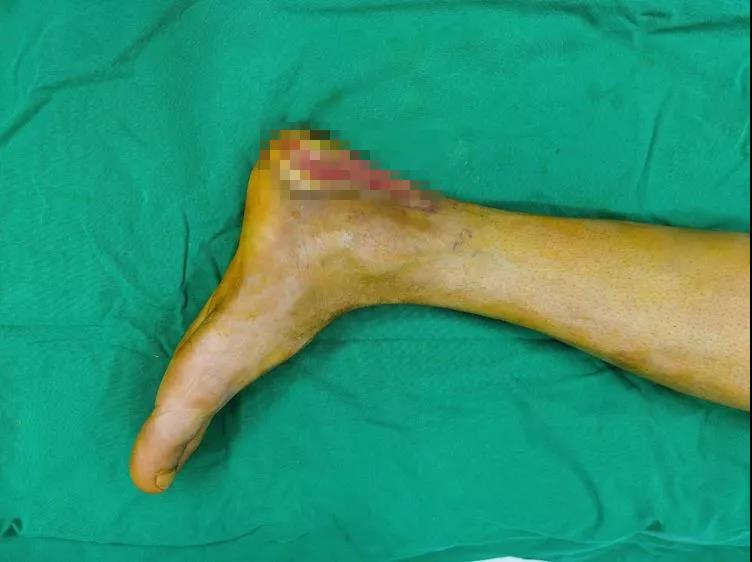

图4:术后一周受区外观